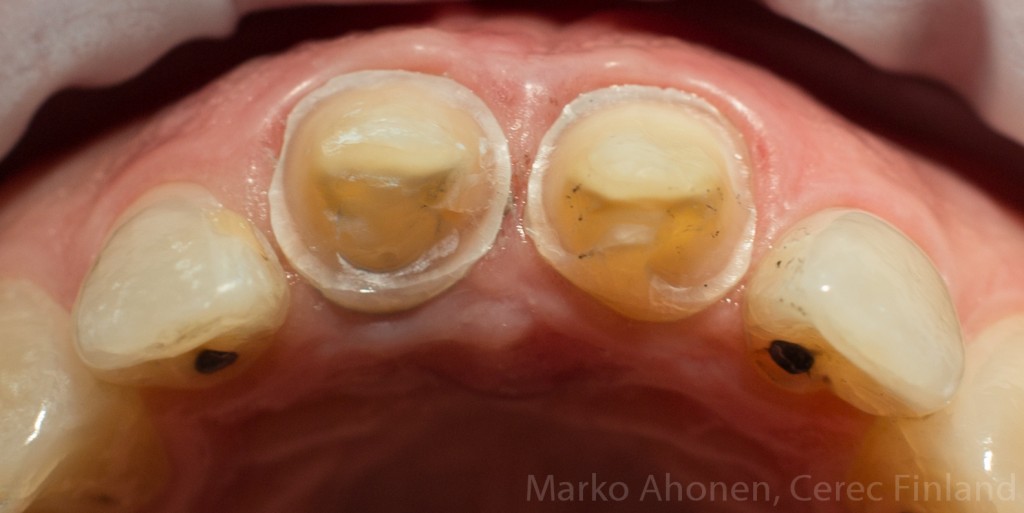

Vanhat paikat ja karies poistettiin ja juurentäytteiden kunto tarkistettiin:

Juurentäytteet suojattiin lasi-ionomeerillä (murtumalinja toisiksi viimeisen hampaan takareunassa heikentää hampaan ennustetta huomattavasti. Paikallisesti syventynyttä ientaskua alueella ei kuitenkaan ollut):